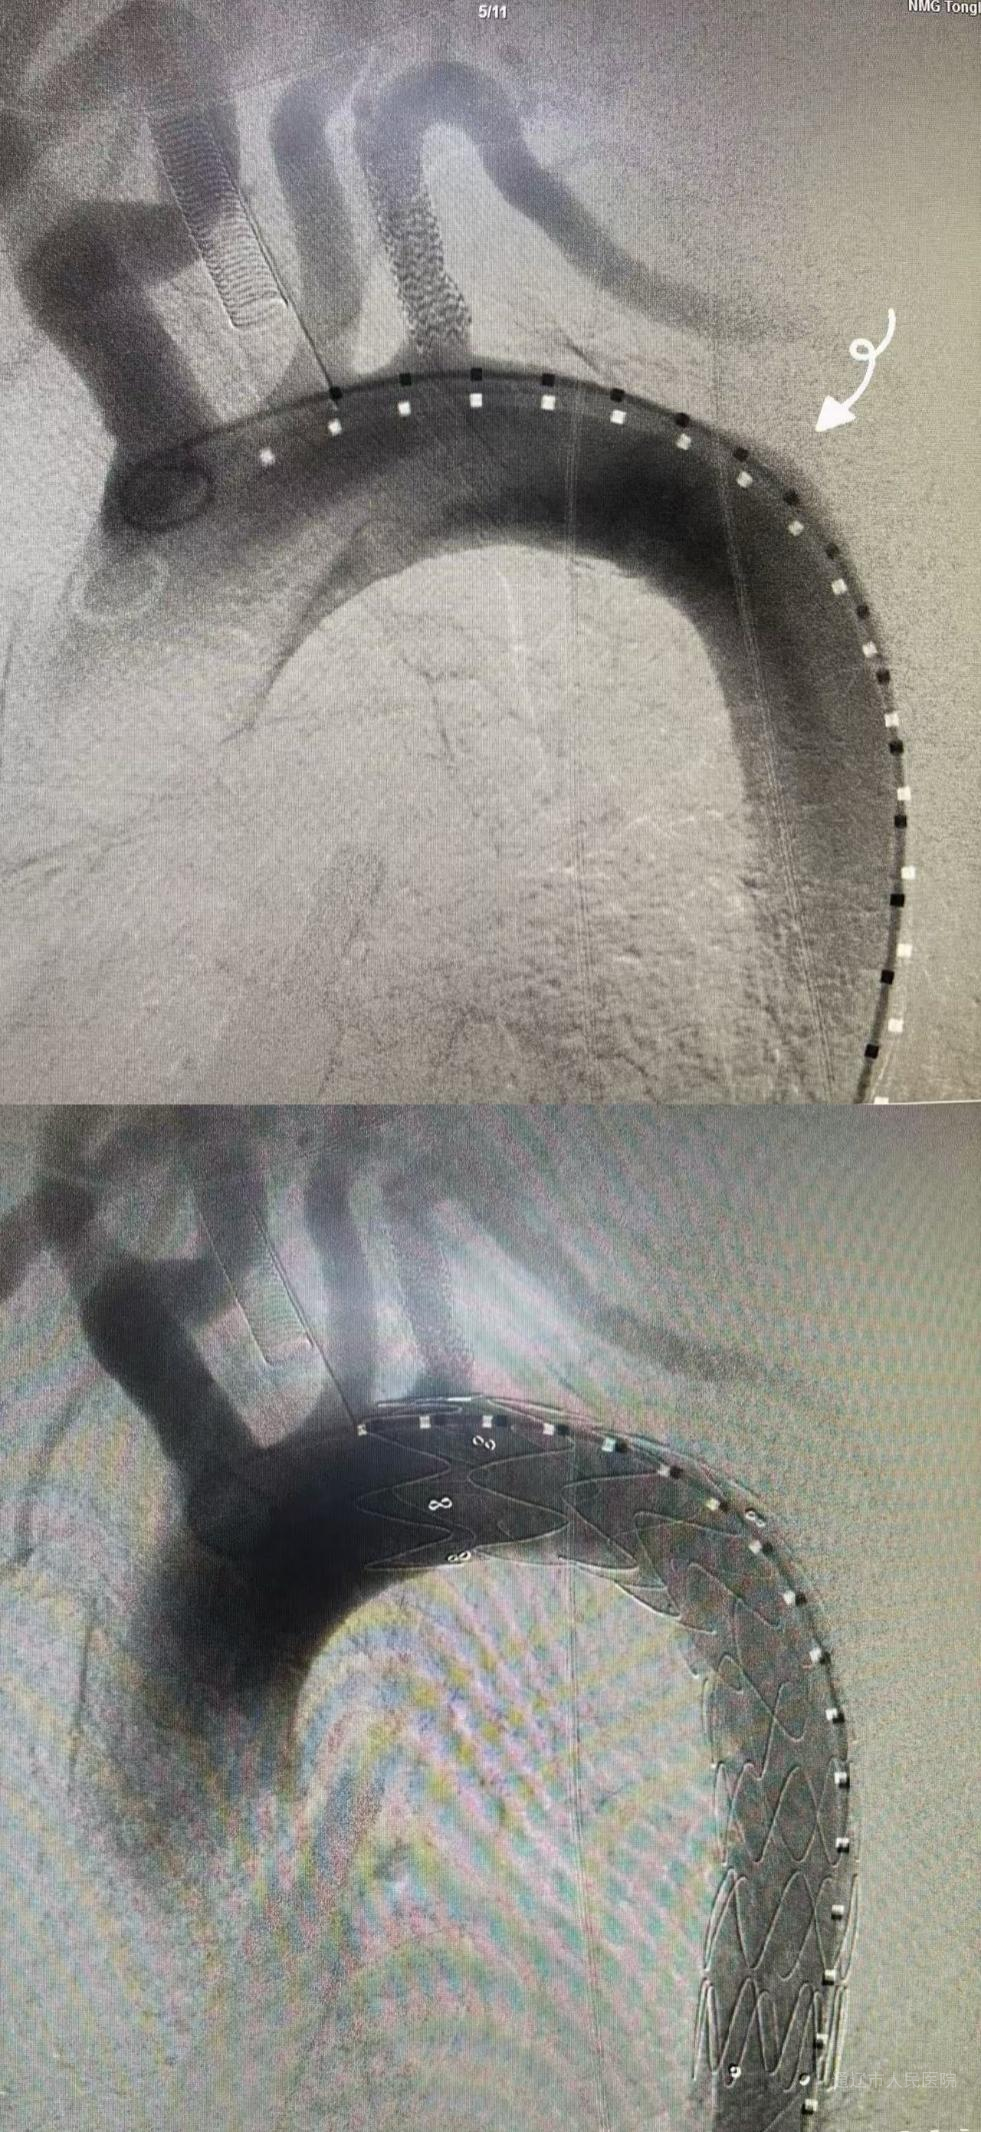

在麻醉科与介入导管室护理团队配合下,手术分阶段推进:心脏血管外科团队先穿刺右侧股动脉,缓慢置入导丝及造影导管,避开主动脉弓溃疡,使用球囊导管预扩左侧锁骨下动脉狭窄处后成功置入左侧锁骨下动脉支架恢复血流,再精准释放胸主动脉覆膜支架隔绝溃疡风险,支架位置良好,无内瘘。随后心血管内三科团队接力,通过同一股动脉入路,运用支架对吻技术、震波球囊、血管内超声的技术,成功实施“冠状动脉支架置入术”,恢复心肌供血。术后患者转入ICU监护,次日病情平稳转回普通病房,在心脏血管外科医护团队精细的围术期管理下,患者恢复良好,顺利出院。